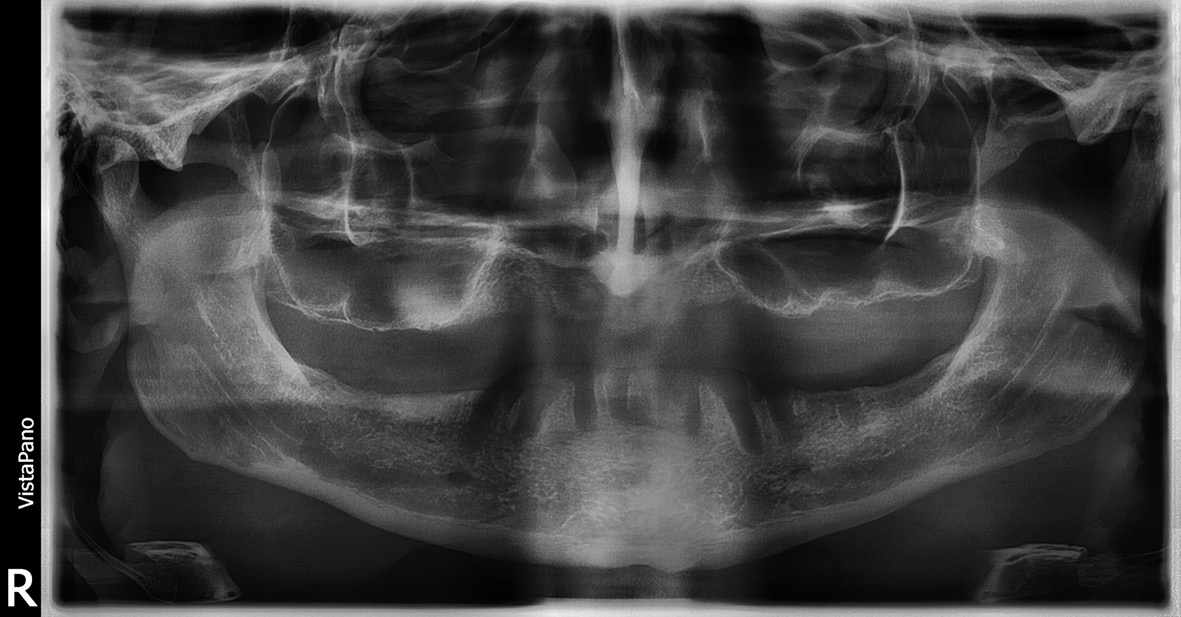

- DVT-Analyse mit Röntgenschablonen, die das zuvor erarbeitete prothetische Ziel radiologisch sichtbar machen.

- Virtuelle Planung der möglichen Implantatpositionen und Evaluation, ob eine festsitzende Versorgung ohne Beckenkammaugmentation durchführbar ist. Die Analyse ergab, dass eine Versorgung im Oberkiefer mit acht Implantaten und im Unterkiefer mit sechs Implantaten für ein festsitzendes Zahnersatz-Konzept zwar implantologisch anspruchsvoll, aber durchführbar wäre. Daraufhin wurden die optimalen Implantatpositionen sowohl in Bezug auf den verfügbaren Knochen als auch das prothetische Ziel definiert und in der Planungssoftware (coDiagnostiX) festgelegt (Abb. 3-5).

Im vorgestellten Fall konnte eine festsitzende Versorgung trotz eines zum Teil extrem kompromittierten Knochenangebotes realisiert werden. Die Erfahrung zeigt hierbei, dass gerade komplexe Planungen am besten im Team aus Zahntechniker und Behandler gemeinsam erarbeitet werden. Besonderes Augenmerk wurde im vorliegenden Fall auf die knöcherne Abstützung der Schablonen gelegt, da im zahnlosen Kiefer eine sichere Lagefixierung der Bohrschablonen nur über Knochenauflagen oder über temporäre Hilfsimplantate erreicht werden kann. Diese sichere Fixierung stellt aber eine conditio sine qua non in der computernavigierten Implantologie dar und ist für die Genauigkeit der Übertragung der geplanten Implantatpositionen entscheidend [8]. Die Möglichkeit zur „flapless Surgery“, also die Implantate direkt transgingival zu setzen, besteht dabei nur bei zahngetragenen Bohrschablonen oder bei der Verwendung von Hilfsimplantaten. Da alle Navigationssysteme zwangsläufig eine technisch begrenzte Genauigkeit aufweisen, muss hierbei ein ausreichender Sicherheitsabstand zu anatomisch kritischen Strukturen bei der Implantatplanung mit berücksichtigt werden [9].